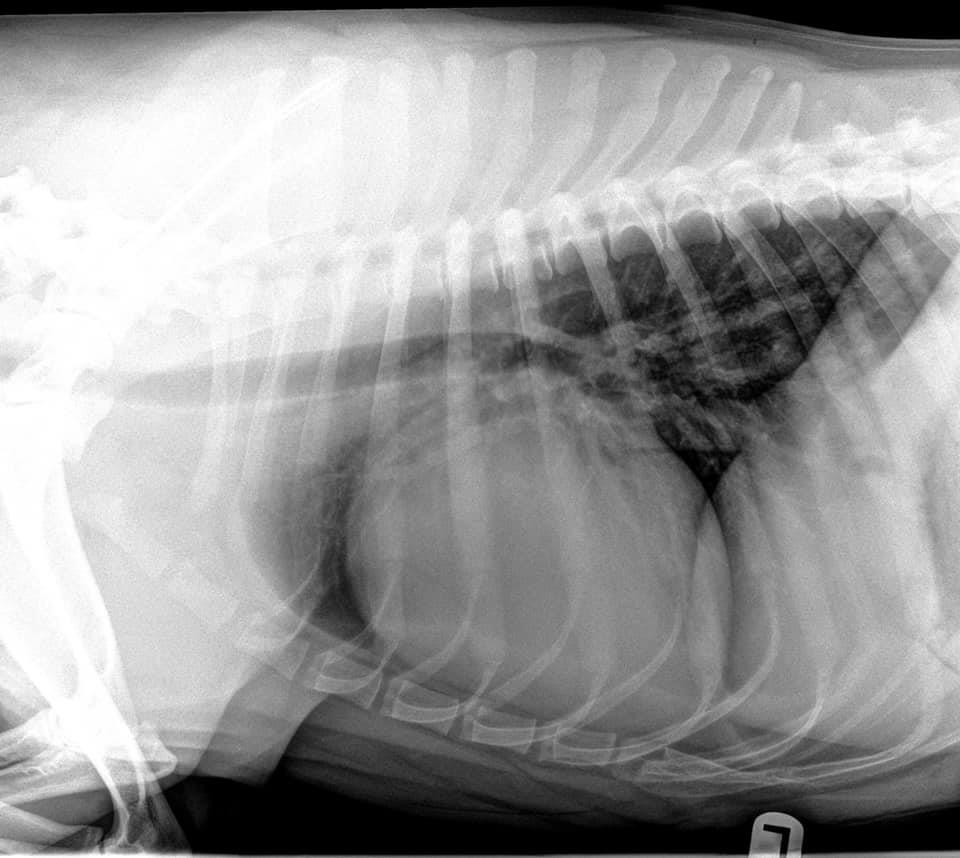

Our local veterinary hospital is seeing young dogs who should not get DCM with severely enlarged hearts. Just recently they posted radiographs of a heart that belongs to a 3-year-old Lab cross. Cardiac ultrasound confirmed the dog has dilated cardiomyopathy (DCM).

The x-rays below belong to a second young dog who has been diagnosed with DCM that day and tenth this summer alone. It is not a large hospital.

The sad part is that this is the second young dog today, and our tenth this summer to be diagnosed with DCM.

Walden Animal Hospital